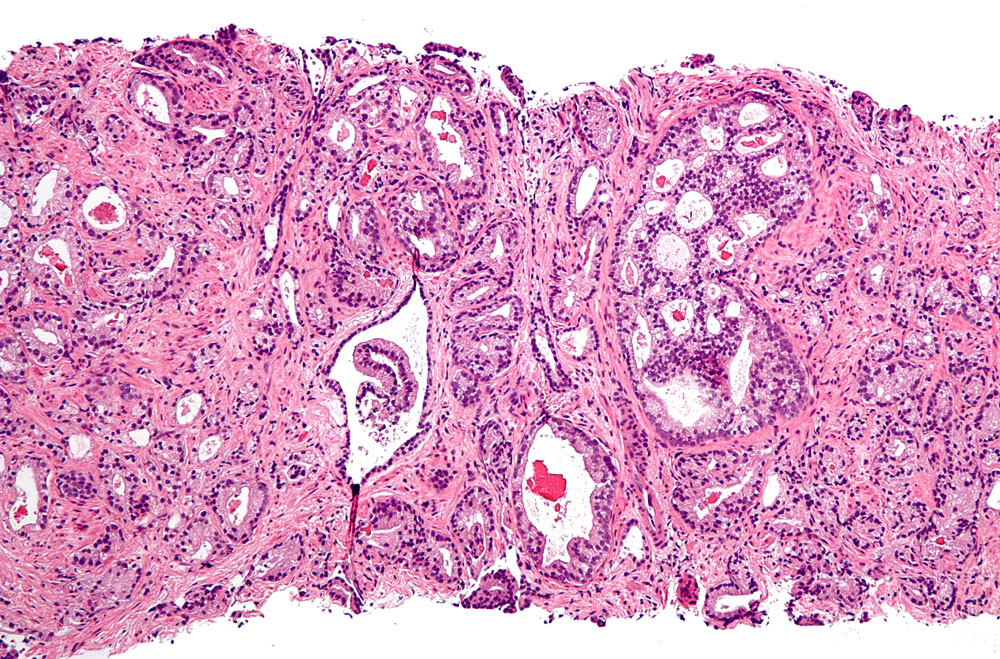

The research team identified specific genetic mutations and patterns of gene expression that are found in t-SCNC, but are distinct from the more common type of prostate cancer known as adenocarcinoma. Among the patterns identified in t-SCNC was higher activity of specific “transcription factor” proteins – proteins that switch on production of other proteins that drive cancer growth.

In 160 of the men, there was enough tumor in biopsy specimens to classify the cancer, which was done independently by three different pathologists blinded to clinical and genetic characteristics of the cancers. They found t-SCNC in specimens from 27 of these men. The researchers surveyed genetic mutations and gene activation within tumor cells and identified patterns of genetic mutations that were associated with t-SCNC and with worse survival.